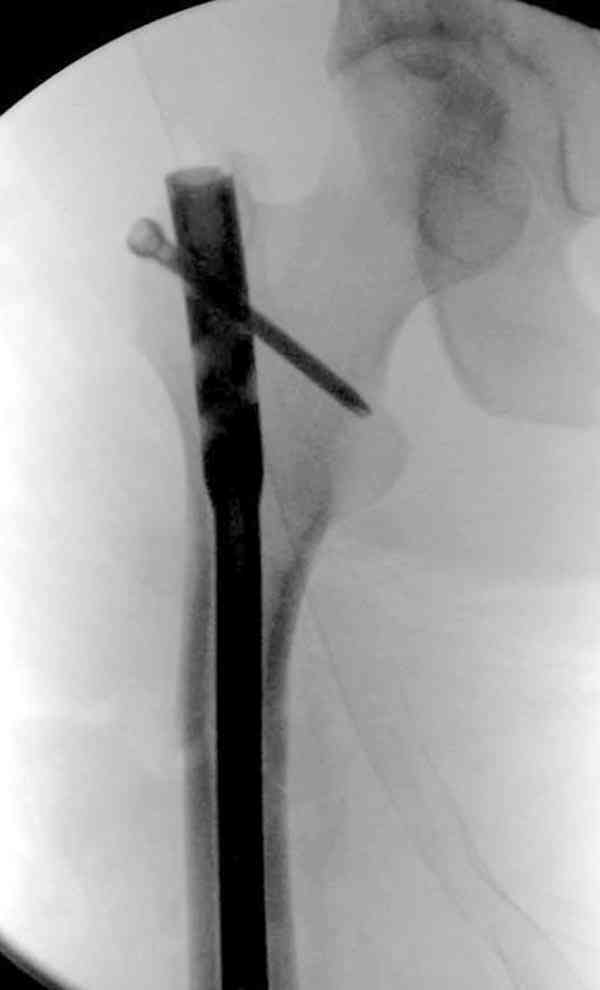

Если имеете доступ к trochanteric медуллярным штифтам TAN Smith Nephew или DePuy, где имеется offset на 8 градусов для удобства черезвертельного введения и профилактики нарушения кровеснабжения

головки (см. снимок) можно было применить штифт, в котором опороспособность достигается за счет блокирующих шурупов сверху и снизу.

На сегодня редко используются прямые piriformis штифты для антеградного введения. И универсальный Versanail от DePuy, выпускаемый для ретро-и антеградного применения с различными вариантами блокировки, в основном применяется для ретроградного введения.

Учитывая, что ложный сустав с укорочением, для восстановления необходимо применение дистракции (на кольцах или femoral distractor) или другой методикой, например после определения длины, штифт вводят в канал, не снимая Insertion tool, блокируется дистально шурупами и дальше штифт доводится до желаемого положения, затем через jig

производят блокировку проксимально